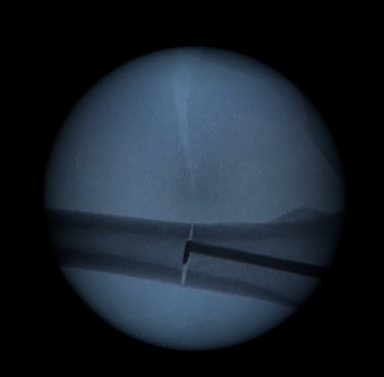

Kit de scies intramédullaires

Notre kit de scies intramédullaires facilite la réalisation d’ostéotomie grâce à la sortie progressive de la denture.